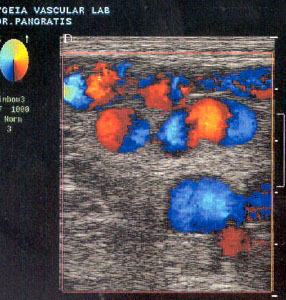

Åëåã÷ïò ëáãïíßùí , ìçñéáßùí êáé éãíõáêþí áñôçñéþí

Ãéá ôïí Ýëåã÷ï ôùí ëáãïíßùí áñôçñéþí ÷ñçóéìïðïéïýìå ôçí ßäéá ôå÷íéêÞ B-mode real-time êáèþò åðßóçò êáé ãéá ôïí Ýëåã÷ï ôùí ìçñéáßùí áñôçñéþí. ×ñçóéìïðïéïýìå ç÷ïâïëÝá 3,5 êáé 7,5ÌÇÆ áíôßóôïé÷á.

Ç áðüöñáîç ôùí ëáãïíßùí áñôçñéþí ðáñïõóéÜæåôáé êáôÜ ôç óôáôéêÞ áíß÷íåõóç, åíþ ç duplex åîÝôáóç ìáò ðáñÝ÷åé ôç äõíáôüôçôá íá êáèïñßæïõìå åðáêñéâþò ôéò áñôçñéïóêëçñõíôéêÝò áëëïéþóåéò êáé ôéò äéáôáñá÷Ýò ôçò áéìáôéêÞò ñïÞò. Ç áêñßâåéá ôçò ìåèüäïõ ãéá ôá ëáãüíéá áããåßá åßíáé 90-96%.

Ï Ýëåã÷ïò ôùí ìçñéáßùí áñôçñéþí ãßíåôáé ìå ç÷ïâïëÝá 7,5ÌÇÆ duplex êáé Ý÷ïõìå áêñéâÞ óôïé÷åßá ãéá ôçí Ýêôáóç êáé ôïí êáèïñéóìü ôùí áñôçñéïóêëçñõíôéêþí áëëïéþóåùí êáé ôùí äáôáñá÷þí ôçò áéìáôéêÞò ñïÞò.

Å÷ïõìå ôç äõíáôüôçôá íá áíáëýóïõìå ôçí õöÞ ôçò áèçñùìáôéêÞò ðëÜêáò êáèþò åðßóçò êáé ôçí åóùôåñéêÞ åðéöÜíåéá ôïõ áããåßïõ, åíôïðßæïíôáò ôçí ýðáñîç åîåëêùìÝíùí áèçñùìáôéêþí ðëáêþí.

Ç áêñßâåéá ôçò ìåèüäïõ ãéá ôç ìçñéáßá êáé éãíõáêÞ áñôçñßá åßíáé 100%. Ç ìçñéáßá áñôçñßá åßíáé ìéá ðñïóöéëÞò ðåñéï÷Þ áèçñùìáôéêþí áëëïéþóåùí êáé áíåõñõóìáôéêÞò íüóïõ.

Ìå ôçí duplex - triplex åîÝôáóç êáèïñßæåôáé óå ðïóïóôü 100% ç Ýêôáóç ôùí áèçñùìáôéêþí áëëïéþóåùí êáèþò åðßóçò êáé ïé äéáóôÜóåéò ôïõ áíåõñýóìáôïò åðß ôçò éãíõáêÞò áñôçñßáò.(5)